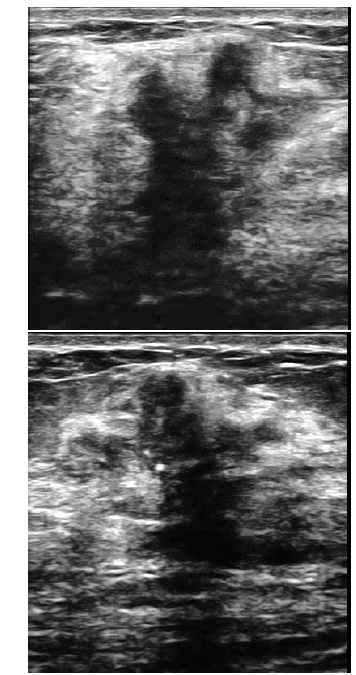

Uma paciente de 32 anos de idade procurou um médico ginecologista por ter palpado nódulo na mama direita. Ao exame das mamas, foi percebido nódulo endurecido, fixo aos planos adjacentes, com cerca de 3 cm de diâmetro. Foi realizada, então, mamografia, que revelou presença de lesão espiculada, com limites imprecisos, retração do parênquima adjacente e microcalcificações pleomórficas agrupadas. O exame ultrassonográfico evidenciou a lesão representada na forma gráfica na figura abaixo.

A respeito dessa situação hipotética, julgue os itens de 75 a 80.

A sombra acústica posterior produzida por essa lesão é determinada pelas microcalcificações presentes no seu interior.

Analisando-se a textura dos nódulos da mama, sabe-se que as lesões marcadamente hipoecogênicas têm maior risco de malignidade. Todavia, cerca de 1/3 dos tumores malignos são isoecogênicos ou discretamente hipoecogênicos em relação ao tecido adiposo.

Microcalcificações são os achados ecográficos que mais elevam o risco de malignidade, quando encontradas em nódulos mamários suspeitos.